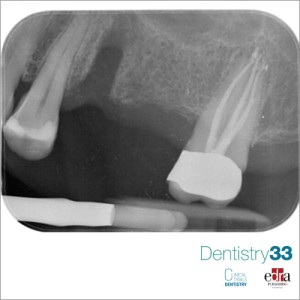

Female patient, 65 years old, requested a visit for widespread pain in the second quadrant, particularly localized in the molar area.The intraoral periapical examination (Fig. 1) reveals bone...

Authors: Prof. Dr. Daniele Cardaropoli, Dr. Alessandro Roffredo

Second of 3 clinical cases in which three-dimensional radiology has allowed us to avoid making diagnostic errors otherwise not evaluable with two-dimensional radiography alone.